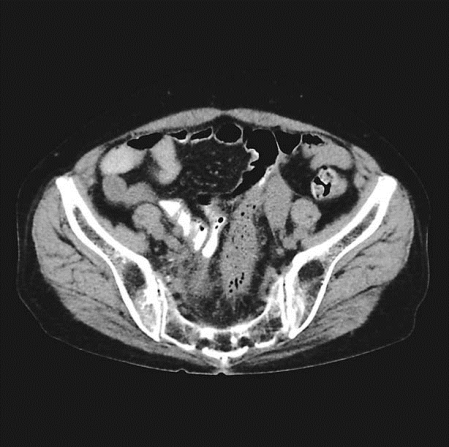

1.影像学检查 超声检查是诊断卵巢异位囊肿和膀胱、直肠内异症的重要方法,可确定异位囊肿位置、大小和形状,其诊断敏感性和特异性均在96%以上。囊肿呈圆形或椭圆形,与周围特别与子宫粘连,囊壁厚而粗糙,囊内有细小的絮状光点。因囊肿回声图像无特异性,不能单纯依靠B型超声图像确诊。盆腔CT及MRI对盆腔内异症有诊断价值,但费用昂贵,不作为初选的诊断方法。

子宫内膜异位症CT